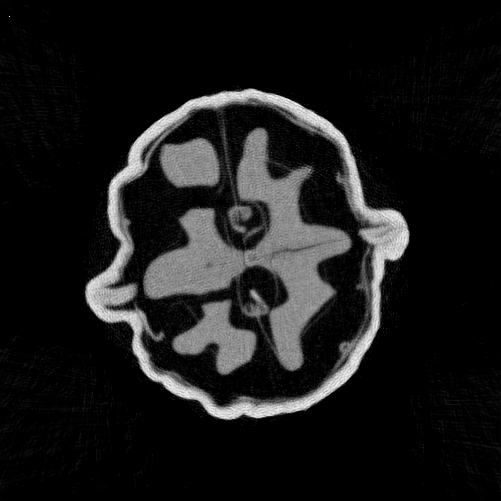

The DIP framework builds on the empirical observation that although neural networks can often fit any signal, some architectures, particularly CNNs, capture natural image structures faster than noise. This behaviour is often linked to the spectral bias of CNNs, whereby low-frequency components (associated with natural image structures) are captured early in the optimisation process, while high-frequency components (associated with noise) are learned later. This tendency can be interpreted as a form of implicit regularisation, often referred to as regularisation by architecture. In the example in Figure 1 we can observe that after 100100 iterations the general outline of the walnut is already visible. Finer details gradually emerge in subsequent iterations.

Refer to caption

Iteration 100100

Iteration 200200

Iteration 400400

Iteration 600600

Iteration 10001000

Figure 1: Vanilla DIP on the μ\muCT walnut with 6060 angles and 128128 detector pixels. We show the DIP reconstruction at different iterations of the optimisation process. Details in Section 6.